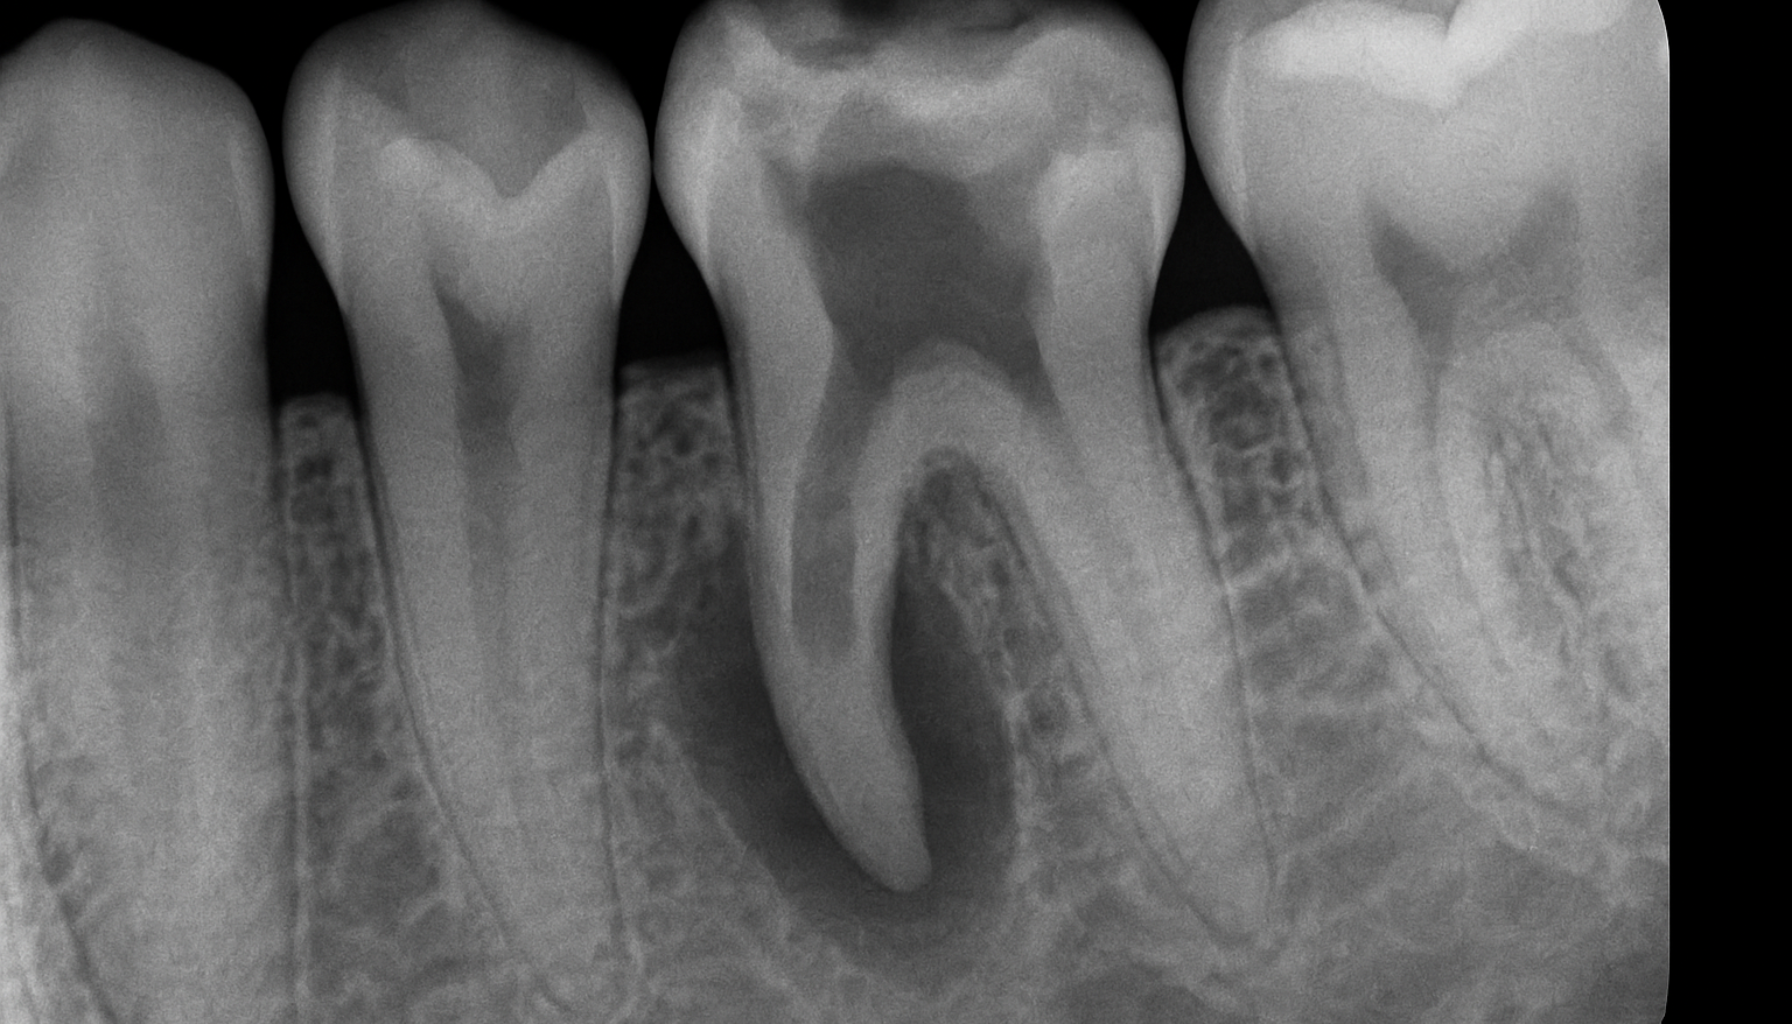

Det finnes to hovedtyper: intern resorpsjon, som starter inne i tannens nervekammer, og ekstern resorpsjon, som begynner fra utsiden av roten. Tilstanden kan utvikle seg i skjul og skade både rot og tannkrone.

Behandling av tannresorpsjon avhenger av typen og hvor langt prosessen har kommet. Ved intern resorpsjon kan det være mulig å stoppe utviklingen med en rotfylling, hvor det betente vevet fjernes og hulrommet fylles. Ved ekstern resorpsjon vurderes ofte kirurgisk inngrep for å fjerne det ødelagte vevet rundt roten.

- Det finnes både intern og ekstern resorpsjon: Intern resorpsjon starter inne i tannen og sprer seg utover, mens ekstern resorpsjon begynner på utsiden – ofte ved roten. Ekstern resorpsjon er mest vanlig og oppdages som regel via røntgen.